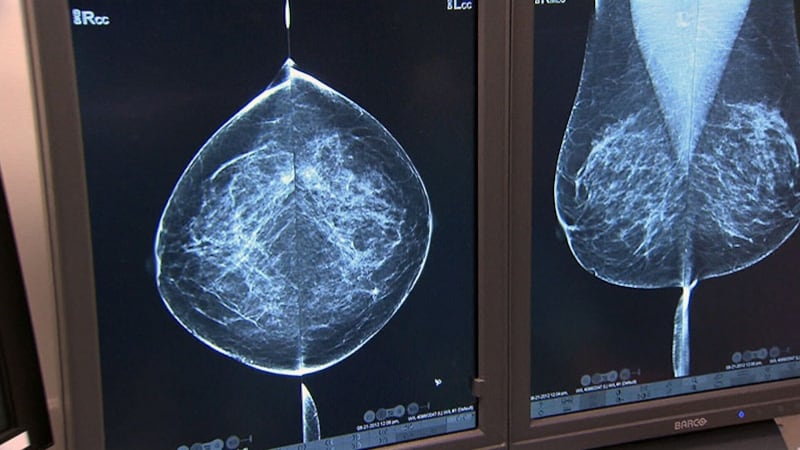

Breast biopsy accuracy varies, especially with pre-cancer conditions: study